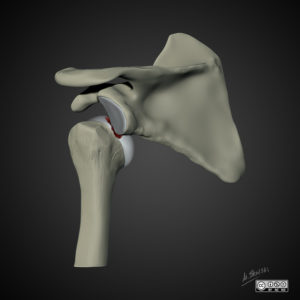

Het schouder gewricht is een zeer mobiel gewricht. De schouderbol en de schouderkom kunnen we vergelijken met een golfbal op een tee. De prijs die we betalen voor deze grote beweeglijkheid is “instabiliteit”.

Om de stabiliteit van de schouder in normale omstandigheden te garanderen beschikken we over een stevig vlies rond de schouder (kapsel) met daarin sterke verstevigingsbanden (gewrichtsbanden). Bijkomend is er een stevige opstaande, kraakbenige ring rond de kom, waar het kapsel zich op vasthecht. Tevens zorgen de rotator cuff spieren (actieve link naar anatomie) voor een bijkomende dynamische stabiliteit, waarbij de rotator cuff de bol gecentreerd houdt in de kom.